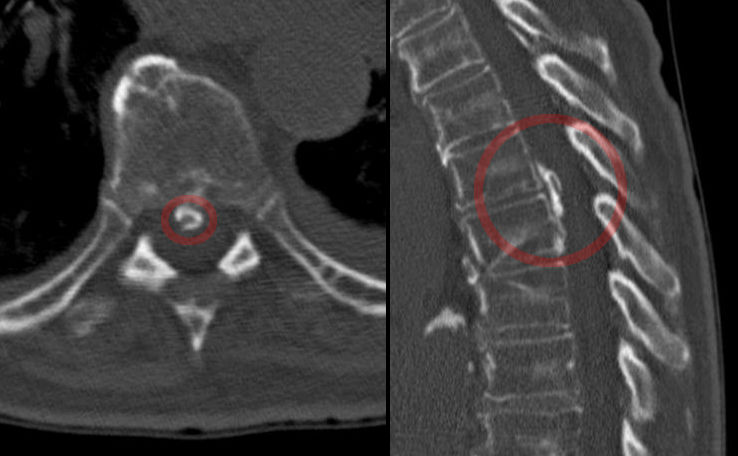

Stages of Ankylosing Spondylosis

Ankylosing spondylitis (AS) is a progressive condition that primarily affects the spine and sacroiliac joints. The progression of AS can vary from person to person, but it typically occurs in several stages, each with its own characteristics and challenges. It’s important to note that not everyone with AS will experience all of these stages, and the severity and timeline can differ. Here are the general stages of ankylosing spondylitis:

- Fusion Begins: As AS progresses, the inflammation can lead to the formation of new bone in the spine, a process known as ossification. This can result in the fusion of spinal vertebrae.

- Reduced Mobility: The fusion of the spine can cause a reduction in spinal mobility and flexibility. The individual may start to experience difficulty in bending, twisting, or turning.

- Severe Spinal Fusion: In the advanced stage, spinal fusion becomes more extensive, and the spine may lose its natural curvature.